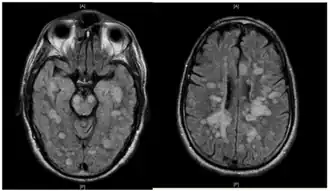

La leucoencefalitis hemorrágica aguda fulminante muestra muchas lesiones. El paciente sobrevivió, pero permaneció en un estado vegetativo persistente | ||

La leucoencefalitis hemorrágica aguda produce múltiples lesiones inflamatorias en el cerebro y la médula espinal, particularmente en la materia blanca. Normalmente se encuentran en la materia blanca subcortical y central y en la unión gris-blanca cortical de ambos hemisferios cerebrales, cerebelo, tronco cerebral y médula espinal,[16] pero la materia blanca periventricular y la materia gris de la corteza, el tálamo y los ganglios basales también pueden estar implicados.